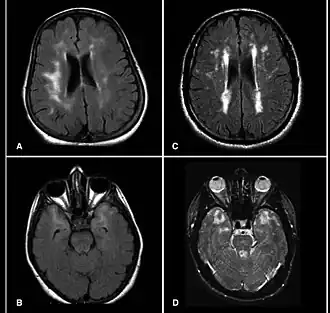

![]() МРТ головного мозга больного синдромом CADASIL | |

CADASIL — от англ. cerebral autosomal dominant arteriopathy with subcortical infarcts and leukoencephalopathy — артериопатия церебральная аутосомно-доминантная с субкортикальными инфарктами и лейкоэнцефалопатией. Заболевание вызвано мутацией гена Notch 3 на 19-й хромосоме[2]. Синдром характеризуется транзиторной ишемической атакой и мигренью, который возникают у пациентов в возрасте от 40 до 50 лет, хотя МРТ может выявить клинические признаки заболевания и раньше[3][4]. В отличие от болезни Бинсвангера у больных отсутствует артериальная гипертензия[5]. Это наследственное заболевание, передающиеся непосредственно от родителей к потомству, имеет аутосомно-доминантный тип наследования.